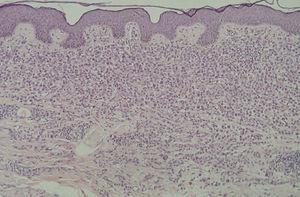

En la HCL el infiltrado se localiza normalmente en la dermis adventicial, y puede invadir la epidermis, produciendo clínicamente lesiones erosivas (figs. 13 y 14). En las formas nodulares puede invadir la hipodermis. En pacientes adultos se ha descrito la distribución del infiltrado alrededor de los anejos (figs. 15 y 16) 13. Aparecen otras células inflamatorias en número variable, sobre todo neutrófilos, eosinófilos, linfocitos y mastocitos y, en menor medida, células gigantes multinucleadas. De forma clásica se han descrito tres subtipos principales: proliferativo, granulomatoso y xantomatoso, que se intentan correlacionar con las diferentes formas clínicas. Histológicamente no existen diferencias entre la HCL y la reticulohistiocitosis congénita autoinvolutiva 7.

Fig. 13.--Infiltrado en placa subepidérmico conformado por células de Langerhans. (Hematoxilina-eosina,x10.)

Fig. 14.--A mayor aumento, detalle del infiltrado en dermis reticular. (Hematoxilina-eosina, x20.)